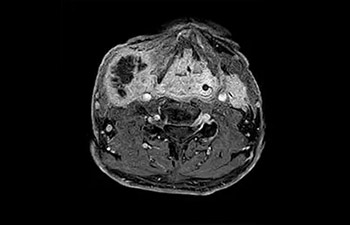

• Es una innovadora técnica de aceleración que no solo permite agilizar las secuencias, sino todo el estudio. • Implementación especial con la que las exploraciones en 2D y 3D pueden llegar a ser hasta un 50% más rápidas con una calidad de imagen prácticamente equivalente.1

• Se puede usar con todos los contrastes y con todas las regiones anatomías.

con Compressed SENSE